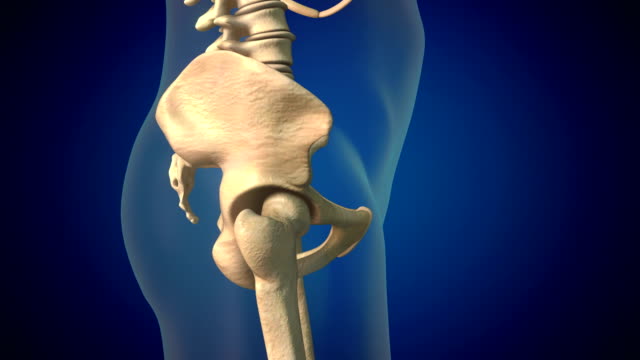

골반의 위쪽, 장골 뼈 주변 부위가 아플 때 주로 중둔근이 문제가 됩니다. 이 근육은 장골능을 감싸고 있는데, 골반이 전방으로 비틀렸을 때 특히 앞으로 이동할 때 이 부위에서 통증이 발생할 수 있습니다. 또한, 흉추나 요추 부분에 문제가 있는 경우에도 이곳에서 통증이 나타날 수 있습니다.

골반 바깥쪽 위쪽 부위가 아프면 대퇴근막장 또는 골반 주변 근육의 문제일 가능성이 높습니다. 골반이 전망으로 비틀릴 때 대퇴근막장이 긴장하며 엉덩이 바깥 부분이 뻐근하게 아프게 됩니다. 고관절을 오래 굴곡시키는 자세나 앉는 자세를 피하고, 관련 근육의 스트레칭을 통해 개선할 수 있습니다.

가운데로 오면 천골과 장골 사이의 천골 관절이 주로 문제가 됩니다. 골반이 뒤로 빠질 때 이 관절 부분에서 통증이 나타날 수 있으며, 이를 바로 잡아주는 치료가 필요합니다. 또한, 천골 주변에 기립근과 인대가 연결되어 있어 이 부위에도 통증이 나타날 수 있으므로 관련 스트레칭을 통해 개선할 수 있습니다.